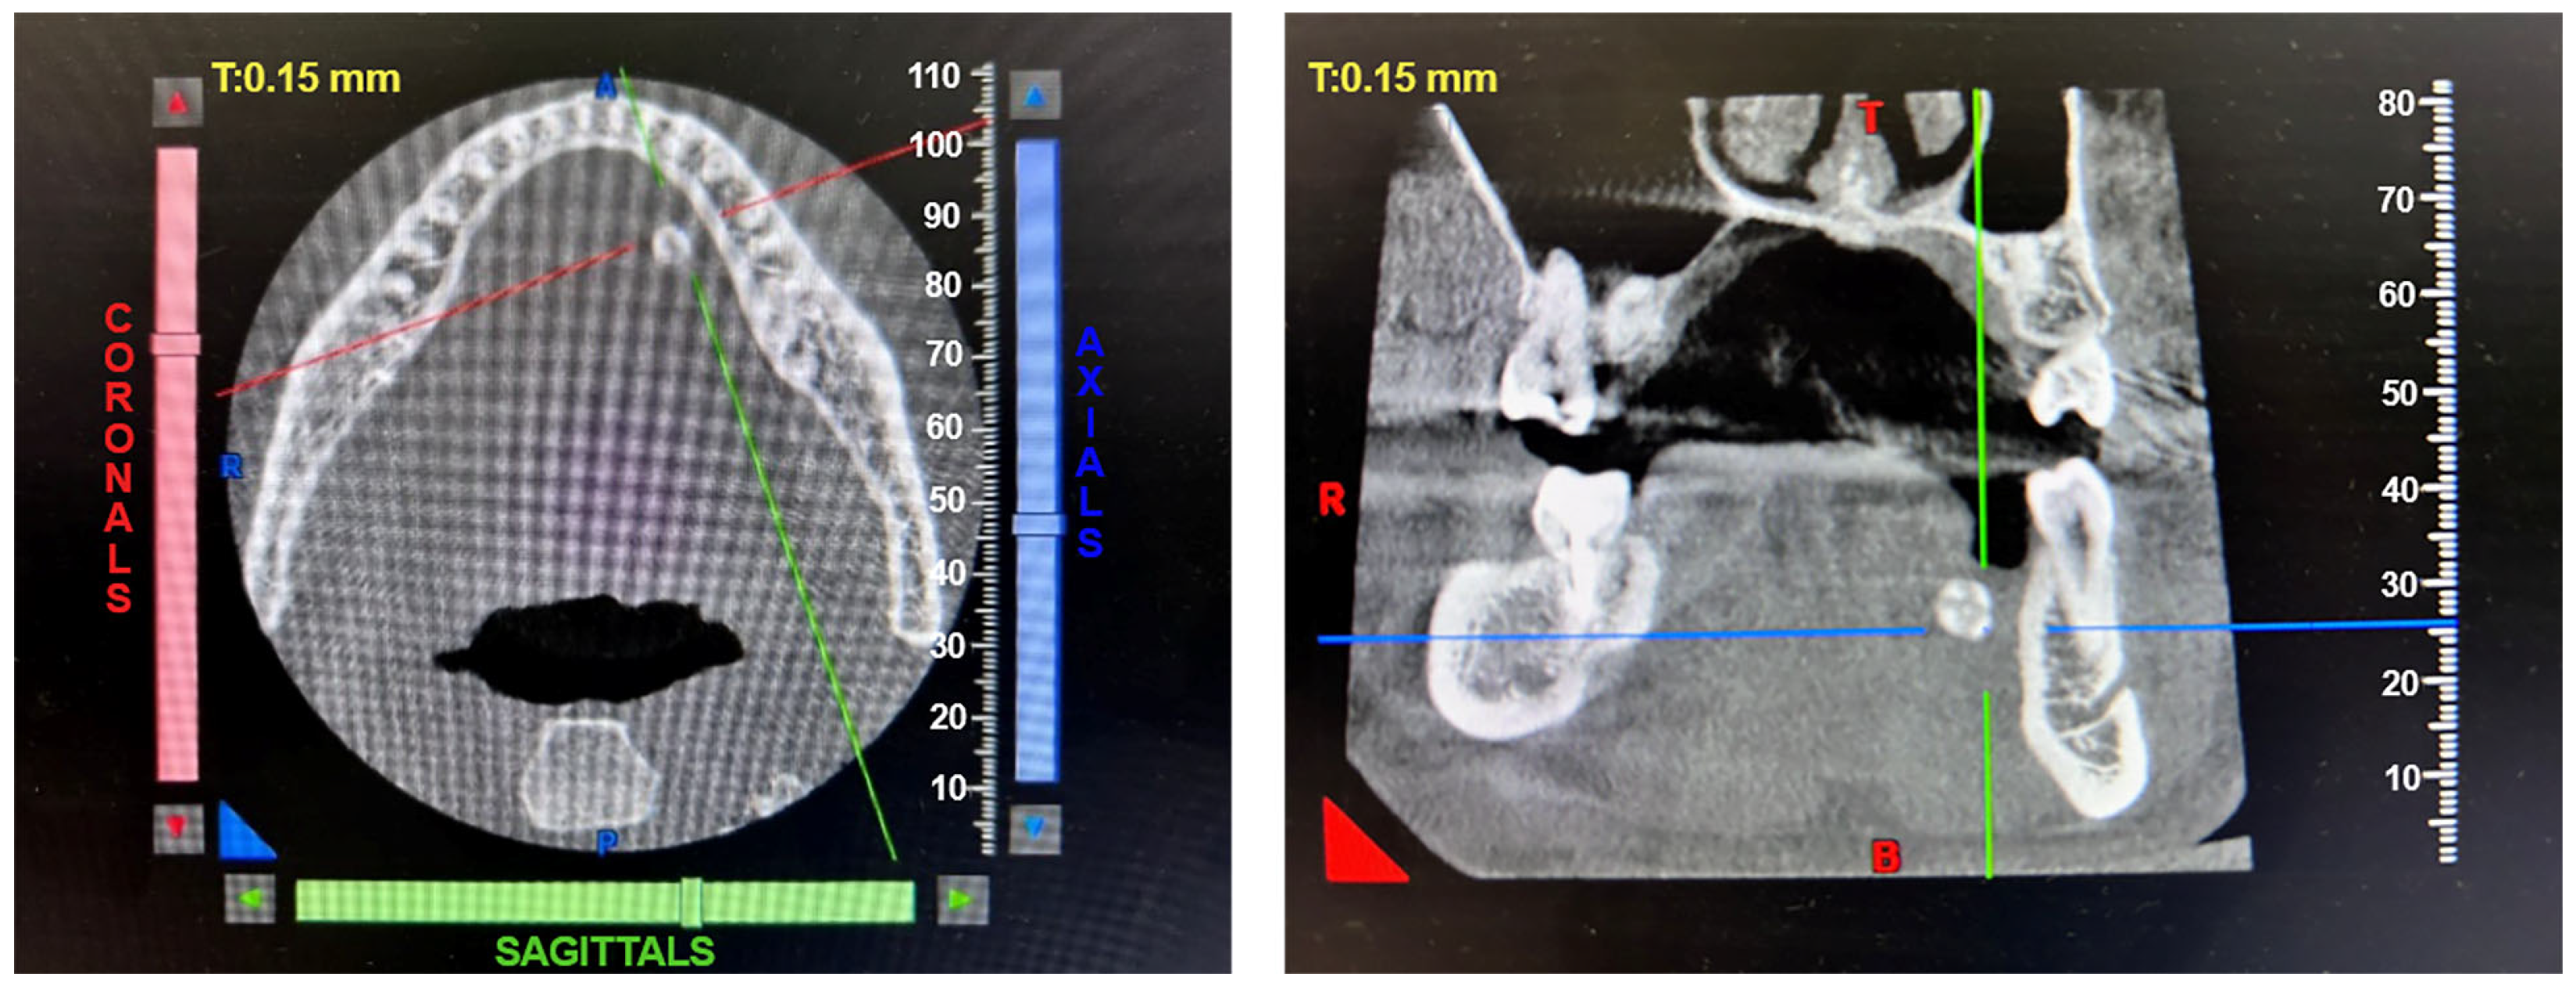

2.1. The Results of X-ray Studies of Salivary Gland Stones

4.1. Clinical Case

4.2. X-ray Micro-CT